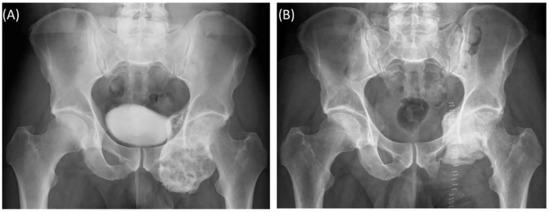

A 59-year-old female patient was diagnosed with bone metastasis of endometrial carcinoma of the sacrum with increasing and immobilizing pain. Primary radiation was discussed, but primary surgery and adjuvant radiation were preferred. Preoperatively, bladder/rectum dysfunction and a bladder-vaginal fistula were already present due to significant metastatic progression. The goal of 3D model-based planning and navigation was marginal resection of the metastasis in terms of a partial sacrectomy below S2 with ligation of the dural tube and the descending nerve roots below S2 (Figure 3 and Figure 4). Repeated revision surgery and systemic antibiotic treatment after wound infection were necessary. At the two-month follow-up, further metastases with pulmonary foci, which did not exist preoperatively, were found. Palliative treatment and radiation followed.

Figure 6. Case 3: Preoperative radiographs in frontal (A) and lateral (B) views, red circles indicate the bony tumor mass; postoperative radiographs in frontal (C) and lateral (D) views.